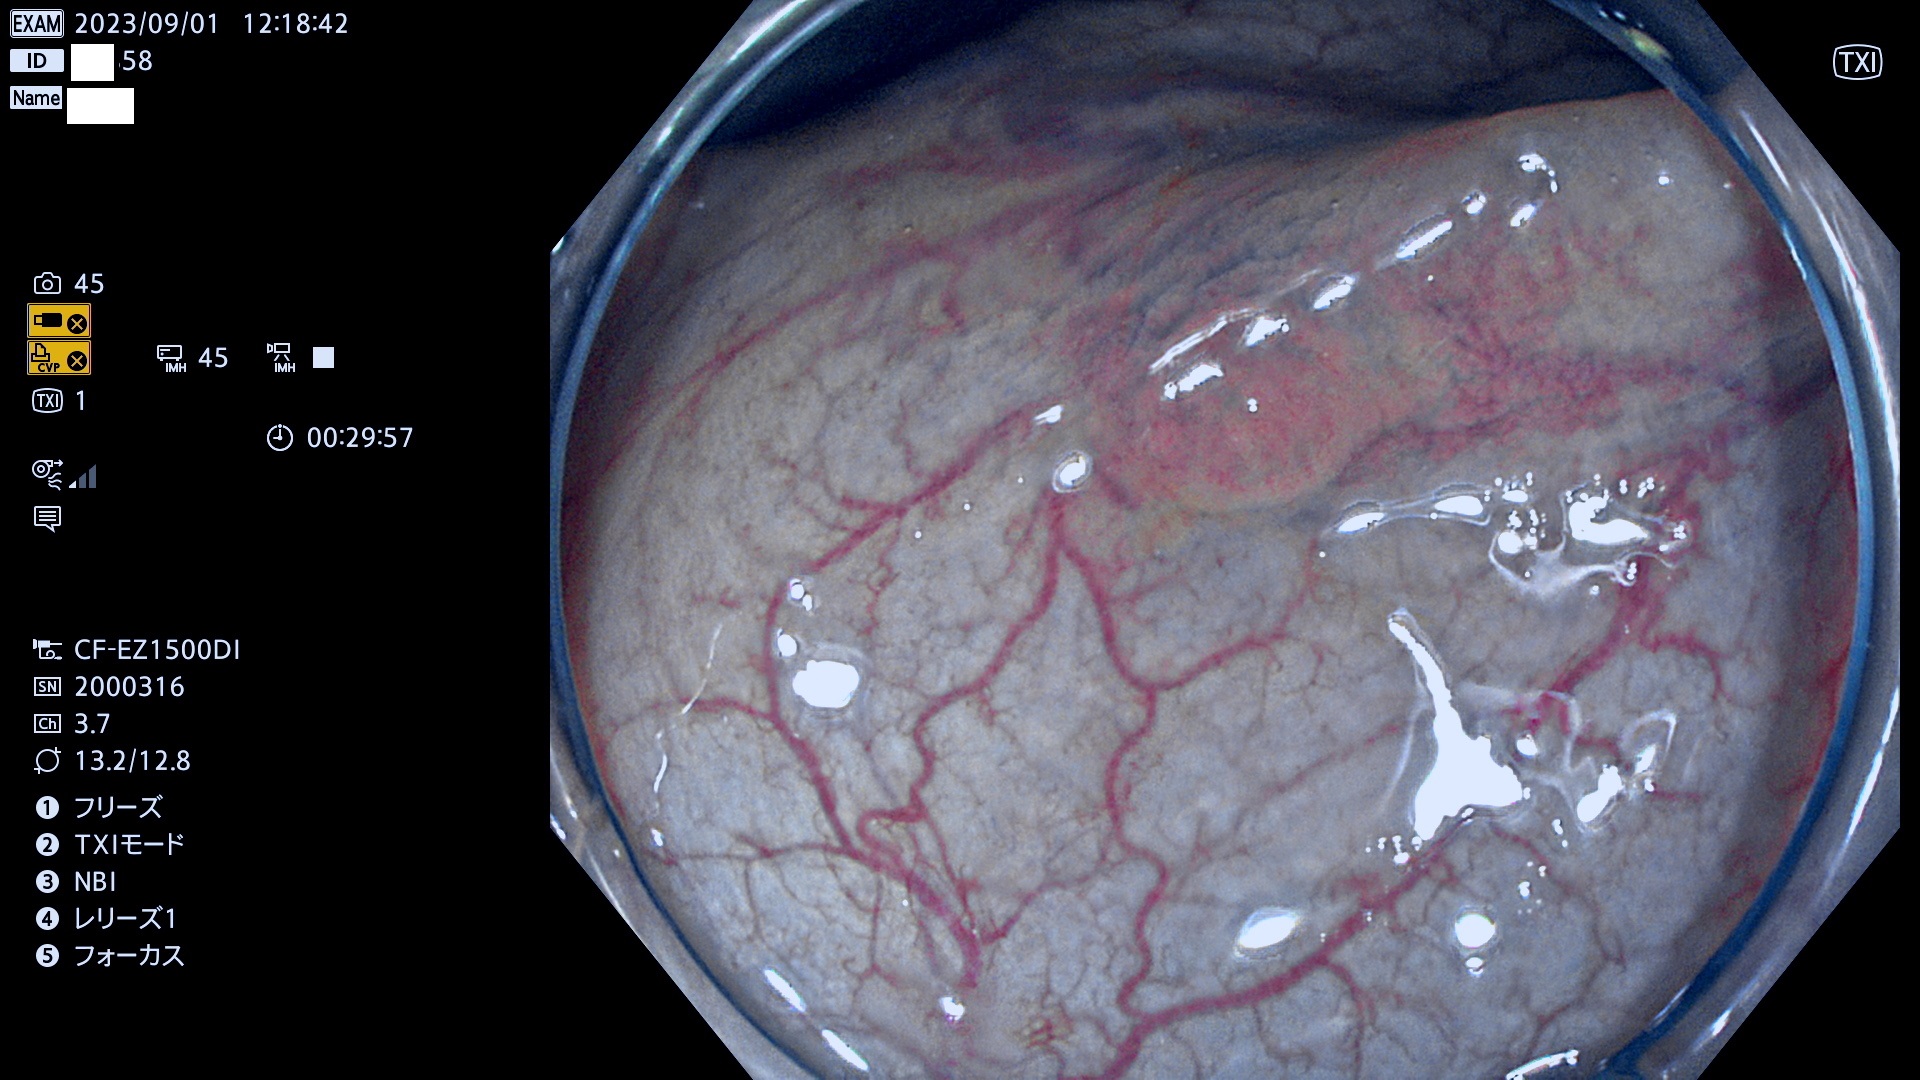

表面型腺腫(Flat Adenoma)の中で、完全に平坦な物をUb、陥凹している物をUcと呼びます。平坦隆起型(Ua)よりも、発見が難しく危険な病変です。このタイプは「内視鏡後・大腸癌の重要犯人」であり、この発見率は「腺腫発見率」よりも、重要な意味があります。

毎週の検査(木・金・土・日)に発見されたUb、Uc型・腺腫を、その週の日曜の夜にUPし1週間、提示します。

抽出の対象期間 2023年8月31日(木)〜9月3(日)の4日間(48件の検査)12件